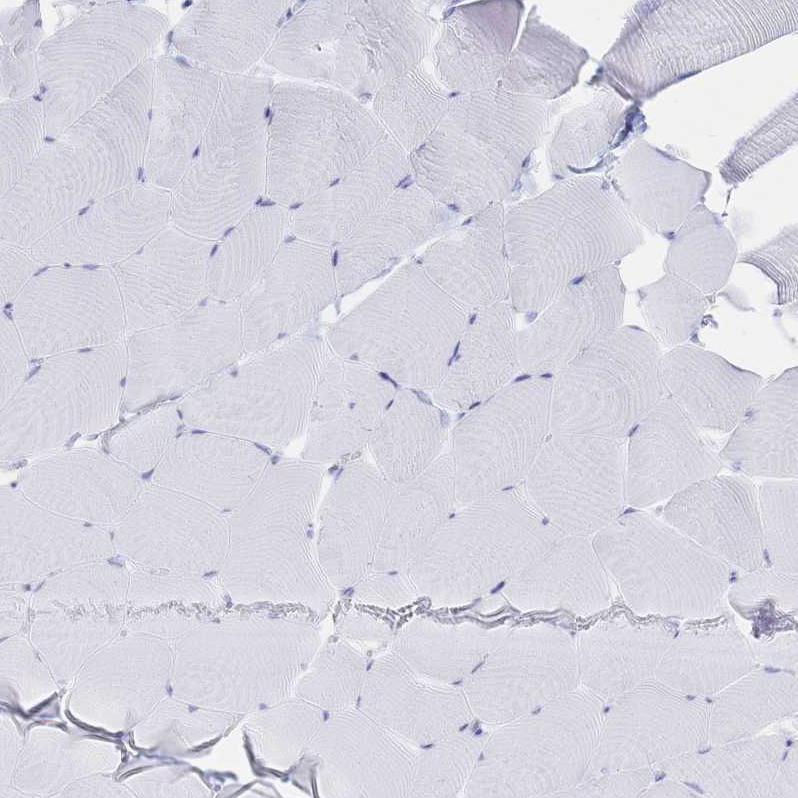

Immunohistochemical staining of human skeletal muscle shows no positivity in myocytes as expected.